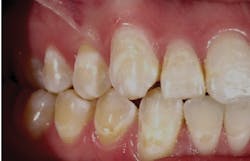

Figure 1 : Courtesy of Merrillville Family Dental Care in Merrillville, Ind.

I am not a full-time practicing hygienist. Thus, as a consultant, I selected one of my best offices and requested that they run a clinical trial that I monitored very closely. Dr. Chanbo Sim is a general dentist who is the owner of Merrillville Family Dental Care in Indiana. The clinical evidence from the trial included before-and-after pictures that were so astonishing that I wanted to share the evidence about this product with all of my offices throughout the United States.

It is important to understand two things about dental consulting in regard to products. Does the product offer real results that I can see with my own eyes, and is the product backed by research at the highest level? When I decide to test a product, I partner with client with whom I have built a long-term relationship. In this case, I chose Dr. Sim. They used Remin Pro on several patients, and I followed the patients from start to finish.

During the process, it is important that the office take a photo of the area of concern when talking about the problem and the consequence. This photo should ideally be taken by an intraoral camera and shared with the patient via computer, iPad, TV, or printed paper. During your explanation you should be able to share before-and-after photos (see Figure 1).